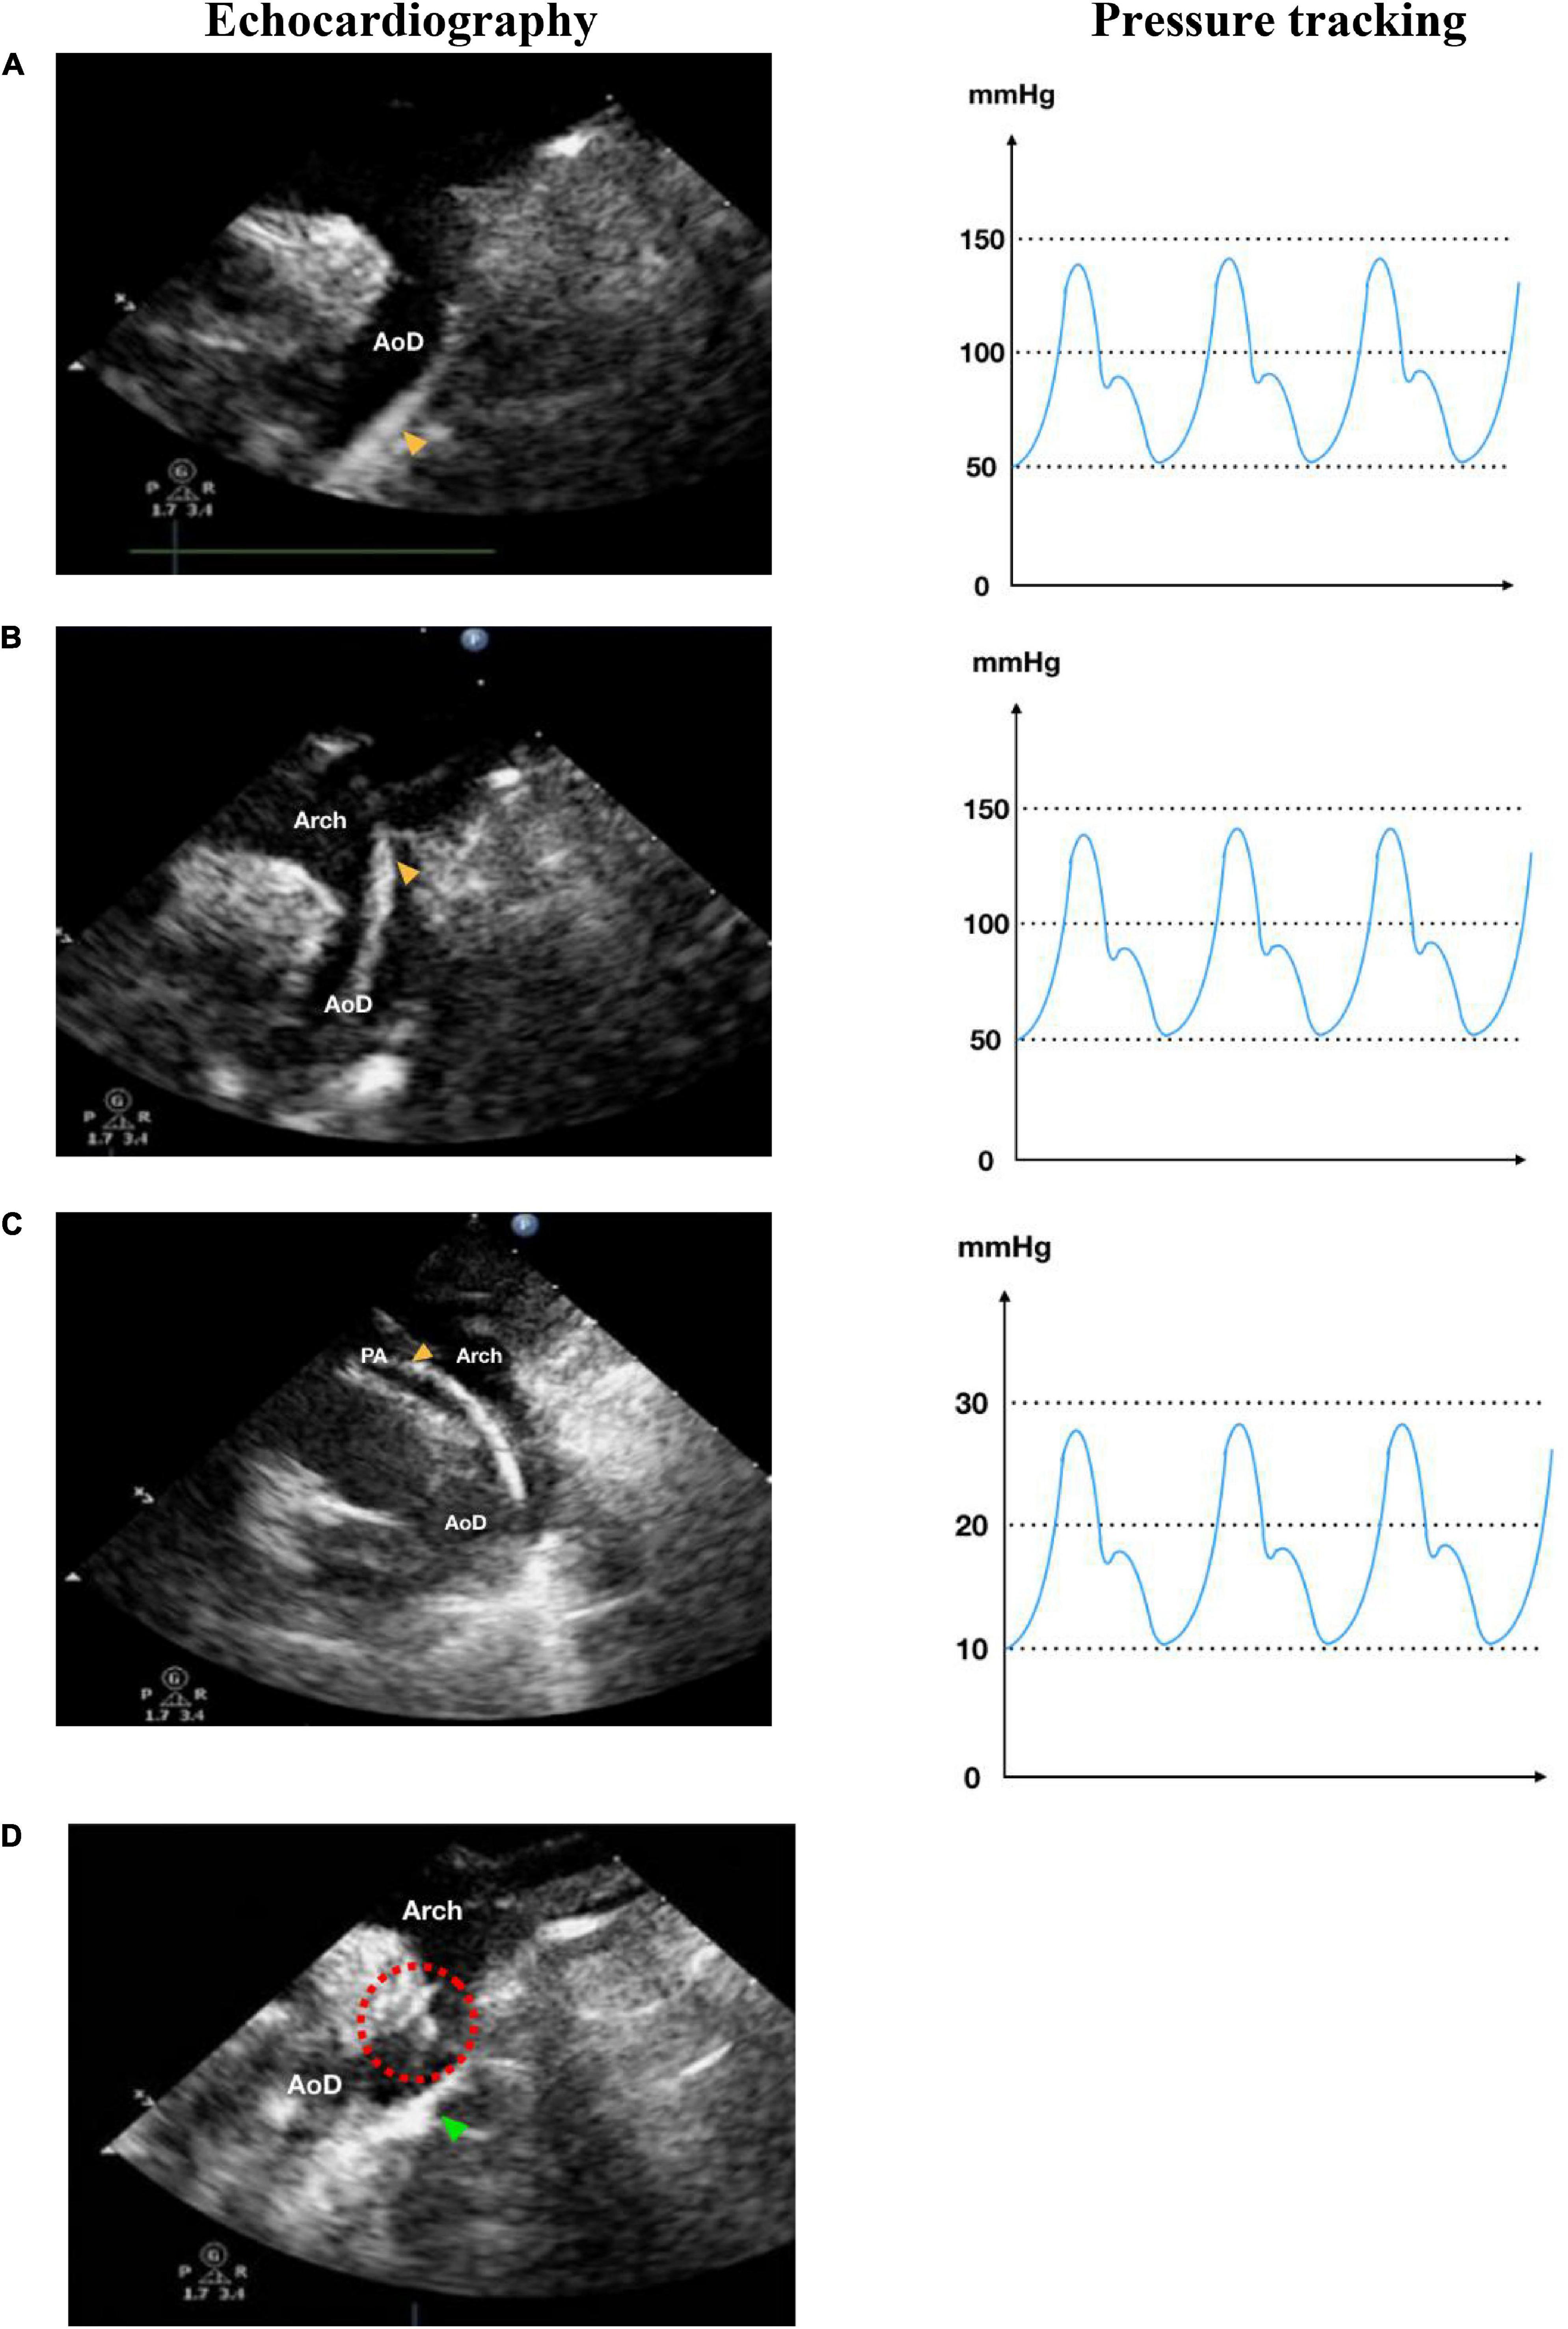

The patients were sedated under general anesthesia (GA) and intubated with an endotracheal tube. At our institution, all pediatric catheterization procedures are performed under general anesthetic. This is because pediatric patients are sometimes uncooperative and may throw a tantrum during the treatment, complicating the procedure. Evaluation of the morphology and diameter of the PDA isthmus and ampulla were measured with the assistance of TTE high parasternal view and/or TEE high esophageal aortic long-axis view (Figure 1). Asepsis and antisepsis in right and left inguinal regions and local anesthesia with 2% lidocaine injection were performed in the femoral region. Venous or arterial access was made by puncturing the femoral vein or artery. A 4–6 French percutaneous sheath with an introducer set was inserted using the Seldinger technique. For diagnostic and interventional purposes, a 4–6 French Judkins Right (JR) guiding, or multipurpose (MP) catheter was used with a 0.025 or 0.035 standard guidewire. Meanwhile, a 7–12 French JR guiding catheter and delivery sheath were used for device implantation. A stepwise approach to antegrade and retrograde percutaneous PDA closure can be seen in Figures 2, 3. The dose of anticoagulant used in our procedure was heparin 50–100 IU/kgBW. While there is no difference in heparin doses for antegrade and retrograde approaches, we would add additional doses if the duration of the procedure exceeds 1 h. Antibiotic cefazolin was given 50 mg/kgBW IV before the occluder device was implanted. Evaluation of the device position, residual shunt, and turbulence in the aorta and pulmonary artery (PA) was made before and after the device detachment from the delivery cable.

FIGURE 3

www.frontiersin.org

Figure 3. Retrograde transarterial approach of percutaneous patent ductus arteriosus (PDA) closure. (A) Catheter is seen in AoD in TTE arch view. (B) Catheter is pushed towards the aortic arch in TTE arch view. (C) In parasternal short axis TTE view as high as the great arteries, the catheter is seen in PA through PDA from AoD. (D) In TTE arch view, the device is stowed in place (shown by red dotted circle) after being delivered from the delivery cable. IVC, inferior vena cava; RA, right atrium; RV, right ventricle; PA, pulmonary artery; Ao, aorta; LA, left atrium; LV, left ventricle; AoD, descending aorta; PDA, patent ductus arteriosus. Orange arrowhead shows the catheter head. Green arrowhead indicates the occluder device.